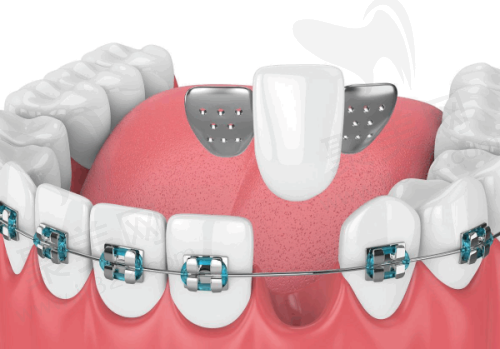

精良的设备对于口腔诊疗至关重要。天津中幸口腔医院拥有数字化口腔CT机、数字化曲面断层全景机、数字化X线机、口腔扫描仪等一系列精良设备。这些设备能够为患者提供精细、效率高、舒适的口腔诊疗服务。比如数字化口腔CT机,它可以清晰地呈现口腔内部的结构,帮助医生更正确地诊断病情。还有口腔扫描仪,能快速获取牙齿的三维模型,为后续的治疗提供严谨的数据。精良的设备不仅提高了诊疗的正确性和效率,也让患者在治疗过程中更加舒适。因此,从设备方面来看,天津中幸口腔医院处于较高的档次。

一家医院的档次,较大程度上取决于医疗团队的实力。天津中幸口腔医院的医疗团队实力雄厚,医生资质正规,都拥有丰富的临床经验。他们擅长各类口腔疾病的诊断与治疗,无论是常见的牙齿问题,还是复杂的口腔疾病,都能为患者提供专精的解决方案。这些医生在口腔领域深耕多年,积累了大量的临床实例,能够根据患者的具体情况制定个性化的治疗方案。就拿种植牙来说,医生们凭借不错的技术和丰富的经验,已经成功帮助众多患者修复了牙齿功能和美观。所以,从医疗团队这方面来看,天津中幸口腔医院达到了较高的档次。